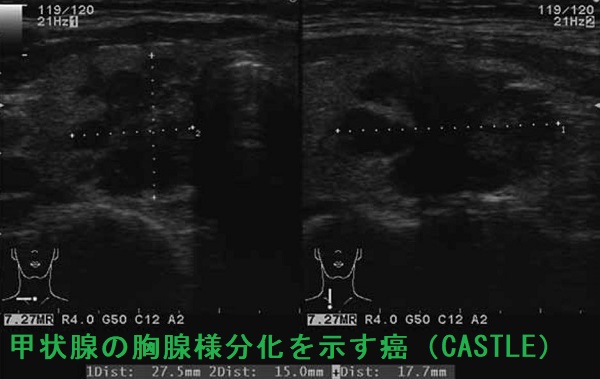

甲状腺の胸腺様分化を示す癌(CASTLE)の超音波(エコー)画像は、甲状腺悪性リンパ腫、甲状腺未分化癌、甲状腺原発扁平上皮癌と鑑別難で、辺縁不整・境界不明瞭、内部は不均一の低エコー結節(あるいは領域)。[Oncol Lett. 2016 Feb;11(2):1321-1326.]